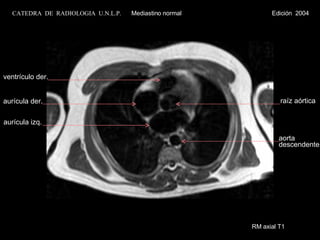

RM axial T1aurícula der. aurícula izq. ventrículo der. raíz aórtica aorta descendente CATEDRA DE RADIOLOGIA U.N.L.P. Mediastino normal Edición 2004